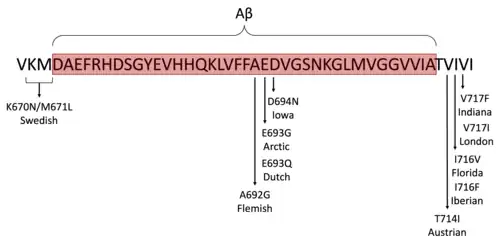

In order to recapitulate and accelerate human Alzheimer's disease pathology, scientists commonly introduce FAD associated mutations.[27] Common genes targeted for genetic engineering in animal models are APP, MAPT, PSEN1, PSEN2, and APOE.[6] This results in the animal models having a higher tendency to form amyloid-β plaques and/or neurofibrillary tangles, the two pathological hallmarks of Alzheimer's disease.[6] These mutated genes can either be over-expressed (first generation models) or expressed at endogenous levels (second generation models) as a way of further replicating disease pathology.[6] Scientists also over-express non-mutated human genes in the hope of seeing similar Alzheimer's disease pathology.[28] These introduced mutations or over-expression of human Alzheimer's associated genes, can lead these animals to additionally display cognitive impairment, deficits in long-term potentiation (LTP), synaptic loss, gliosis, and neuronal loss. As current models are highly reliant on FAD mutations to induce Alzheimer's like pathology, there is still no ideal model that fully replicates SAD (sporadic Alzheimer's disease), which is the most common type of diagnosis in patients.[29]

| APPSwe TgC3-3[28][34] | APP | Express both murine and human APP carrying the Swedish mutation | Murine PrP | Aβ plaques (24-26 mo) |

| Tg2576[28][35] | APP | Over-expresses human APP with the Swedish mutation | Hamster PrP | Synaptic loss (4-6 mo), LTP deficits (4-6 mo), cognitive impairment (4-6 mo), gliosis (10-16 mo), Aβ plaques (11-13 mo) |

| APP23[28][36] | APP | Display a 7-fold over-expression of human APP carrying the Swedish mutation | Murine Thy1 | Cognitive impairment (3 mo), Aβ plaques (6 mo), gliosis (6 mo), neuronal loss (14-18 mo) |

| PDAPP[28][37] | APP | Over-express human APP carrying the Indiana mutation | PDGFβ | Cognitive impairment (3 mo), LTP deficits (4-5 mo), Aβ plaques (6 mo), gliosis (6 mo), synaptic loss (8 mo) |

| TgCRND8[28][38] | APP | Display 5-fold over-expression of human APP carrying the Swedish and Indiana mutations | Syrian hamster PrP | Cognitive impairment (3 mo), Aβ plaques (3 mo), gliosis (3 mo), LTP deficit (6 mo), synaptic loss (6 mo), neuronal loss (6 mo) |

| APPNL-F[39] | APP | Express humanized APP with the Swedish and Iberian mutations | N/A | Aβ plaques (6 mo), gliosis (6 mo), synaptic loss (9-12 mo), cognitive impairment (18 mo) |

| APPNL-G-F[40] | APP | Express endogenous levels of humanized APP carrying the Swedish, Iberian, and Arctic mutations | N/A | Aβ plaques (2 mo), gliosis (2 mo), synaptic loss (4 mo), cognitive impairment (6 mo) |